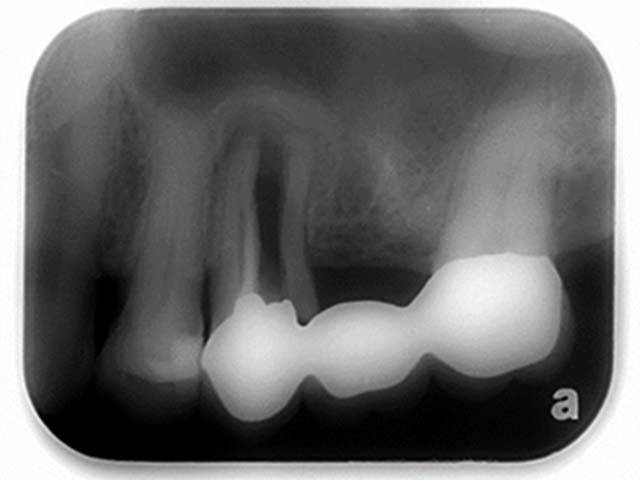

鼻竇增高術(側窗) 首頁 案例分享 人工植牙 鼻竇增高術(側窗) 鼻竇增高術(側窗) 製作多年的牙橋,牙根斷裂,發炎 鼻竇增高術 側面開窗 抬高鼻竇 鼻竇增高術 置入骨粉 覆蓋再生膜,保護骨粉 術後追蹤,傷口良好 裝戴正式假牙 完成 8年追蹤 左上牙根斷裂 植牙重建 九年追蹤